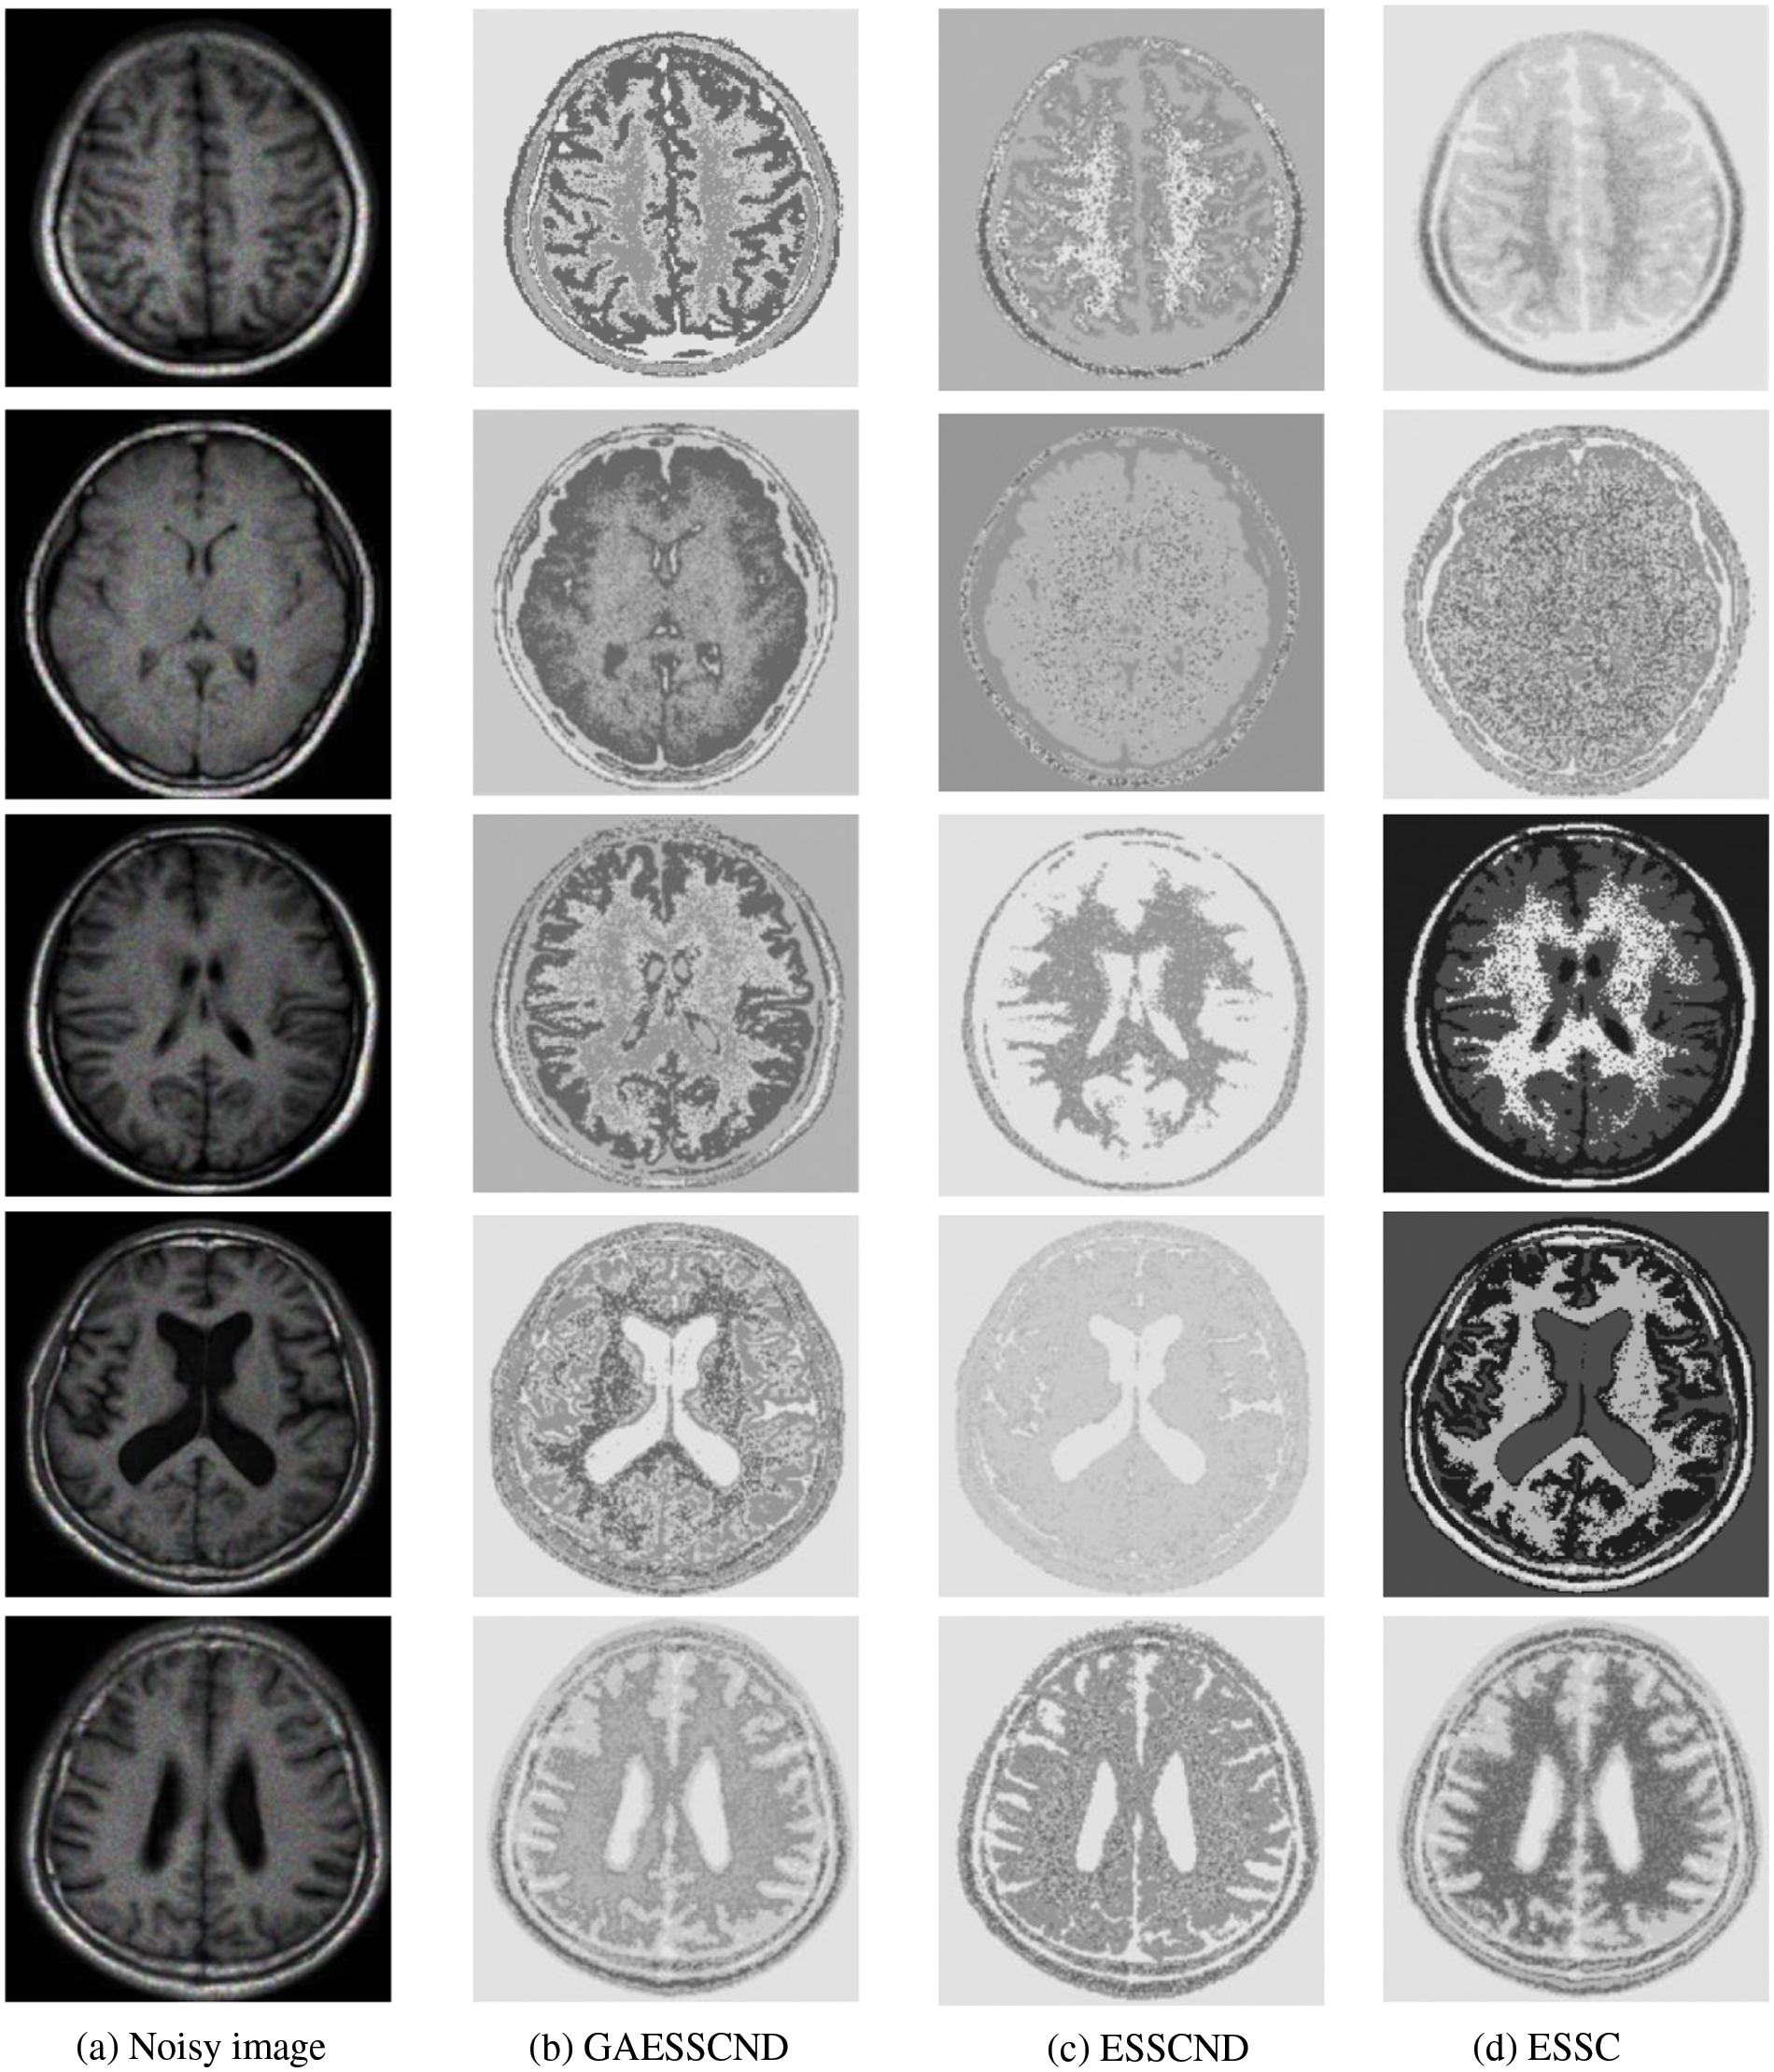

Taking the normal brain database as an example, multiple noise levels were provided, and the noise level pn0 = 0%, 1%, 3%, 5%, 7%, 9%. To verify the anti-noise performance of the algorithm, the highest noise level was selected, and 5 brain images were selected to verify the segmentation effect of the algorithm compared with other soft subspace clustering algorithms. The mode = T1, protocol = ICBM, phantom name = normal, section thickness = 1 mm, noise = 9%, and INU = 0%; brain images of 62 pages, 75 pages, 83 pages, 96 pages, 107 pages were selected. Cluster segmentation was performed for 0 = Background, 1 = CSF, Cerebrospinal Fluid, 2 = Gray Matter, and 3 = White Matter. The effect of segmentation and clustering is shown in Fig. 3:

Figure 3: The segmentation result of the T1-weighted simulated brain MR image, (a) depicts the original image, (b) depicts the standard segmentation result graph for evaluation calculation, (c) depicts the segmentation effect of the GAESSCND algorithm proposed in this paper, (d) depicts the segmentation effect of the ESSCND algorithm, (e) depicts the segmentation effect of the ESSC algorithm, (f) depicts the segmentation effect of the KESSC algorithm that guides the kernel function, (g) depicts the segmentation effect of the FSC algorithm, and (h) depicts the segmentation effect of the entropy weighted EWKM algorithm

In Fig. 3, Column (a) is the clustering algorithm proposed in this paper, and the segmentation effect is obviously better than that of other soft subspace clustering algorithms (b–h). In this chapter, the Rand Index (RI) [45], normalized mutual information (NMI) [46] and accuracy indices are used to evaluate the clustering effect, where RI and NMI are calculated by Eqs. (16) and (17), respectively.

Comparing the data obtained from Table 2, the segmentation effect of the GAESSCND algorithm is very similar to the standard segmentation. The GAESSCND algorithm proposed in this section is compared with four existing soft subspace clustering algorithms, ESSC, EWKM, FSC, and KESSC with a kernel function, and ESSCND with generalized noise detection, where the FSC algorithm is a fuzzy weighted soft subspace clustering algorithm and the EWKM algorithm is an entropy weighted soft subspace clustering algorithm. The ESSC algorithm combines intraclass and interclass information, and the rest of the improved soft subspace clustering algorithms select reasonable parameters in a larger range. The evaluation indices are chosen in 3 ways to determine the noise immunity of the GAESSCND algorithm for noisy MR images. From the displayed visual effect and the 3 evaluation indices, GAESSCND has good noise immunity, and the clustering effect is similar to the standard segmentation. Compared with other soft subspace clustering algorithms, which are not effective in segmenting boundaries and dividing brain regions, the GAESSCND algorithm can clearly divide brain white matter, brain gray matter, cerebrospinal fluid [47] and background regions well so that the problem of noise in MR images of the brain can be handled well.